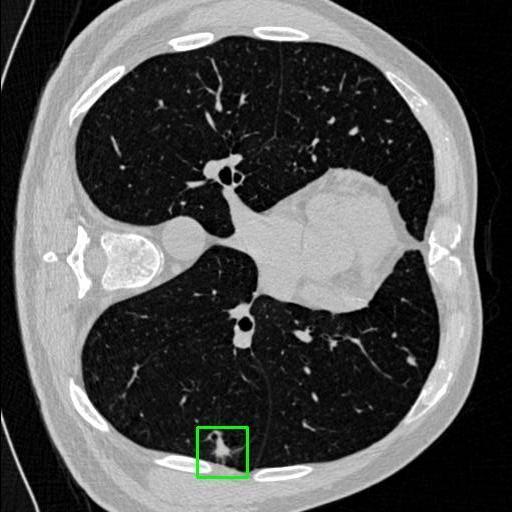

We developed an AI-based system using deep learning models for analyzing lung CT scans to detect and classify pulmonary nodules. We chose the YOLOv11 architecture for its enhanced object detection capability and adapted it specifically for medical imaging, incorporating pixel-level precision and severity classification.

Classification into three severity levels with colored bounding boxes.

Designed a severity classification system that categorizes nodules into null, moderate, and severe using colored bounding boxes, assisting in rapid clinical decision-making.